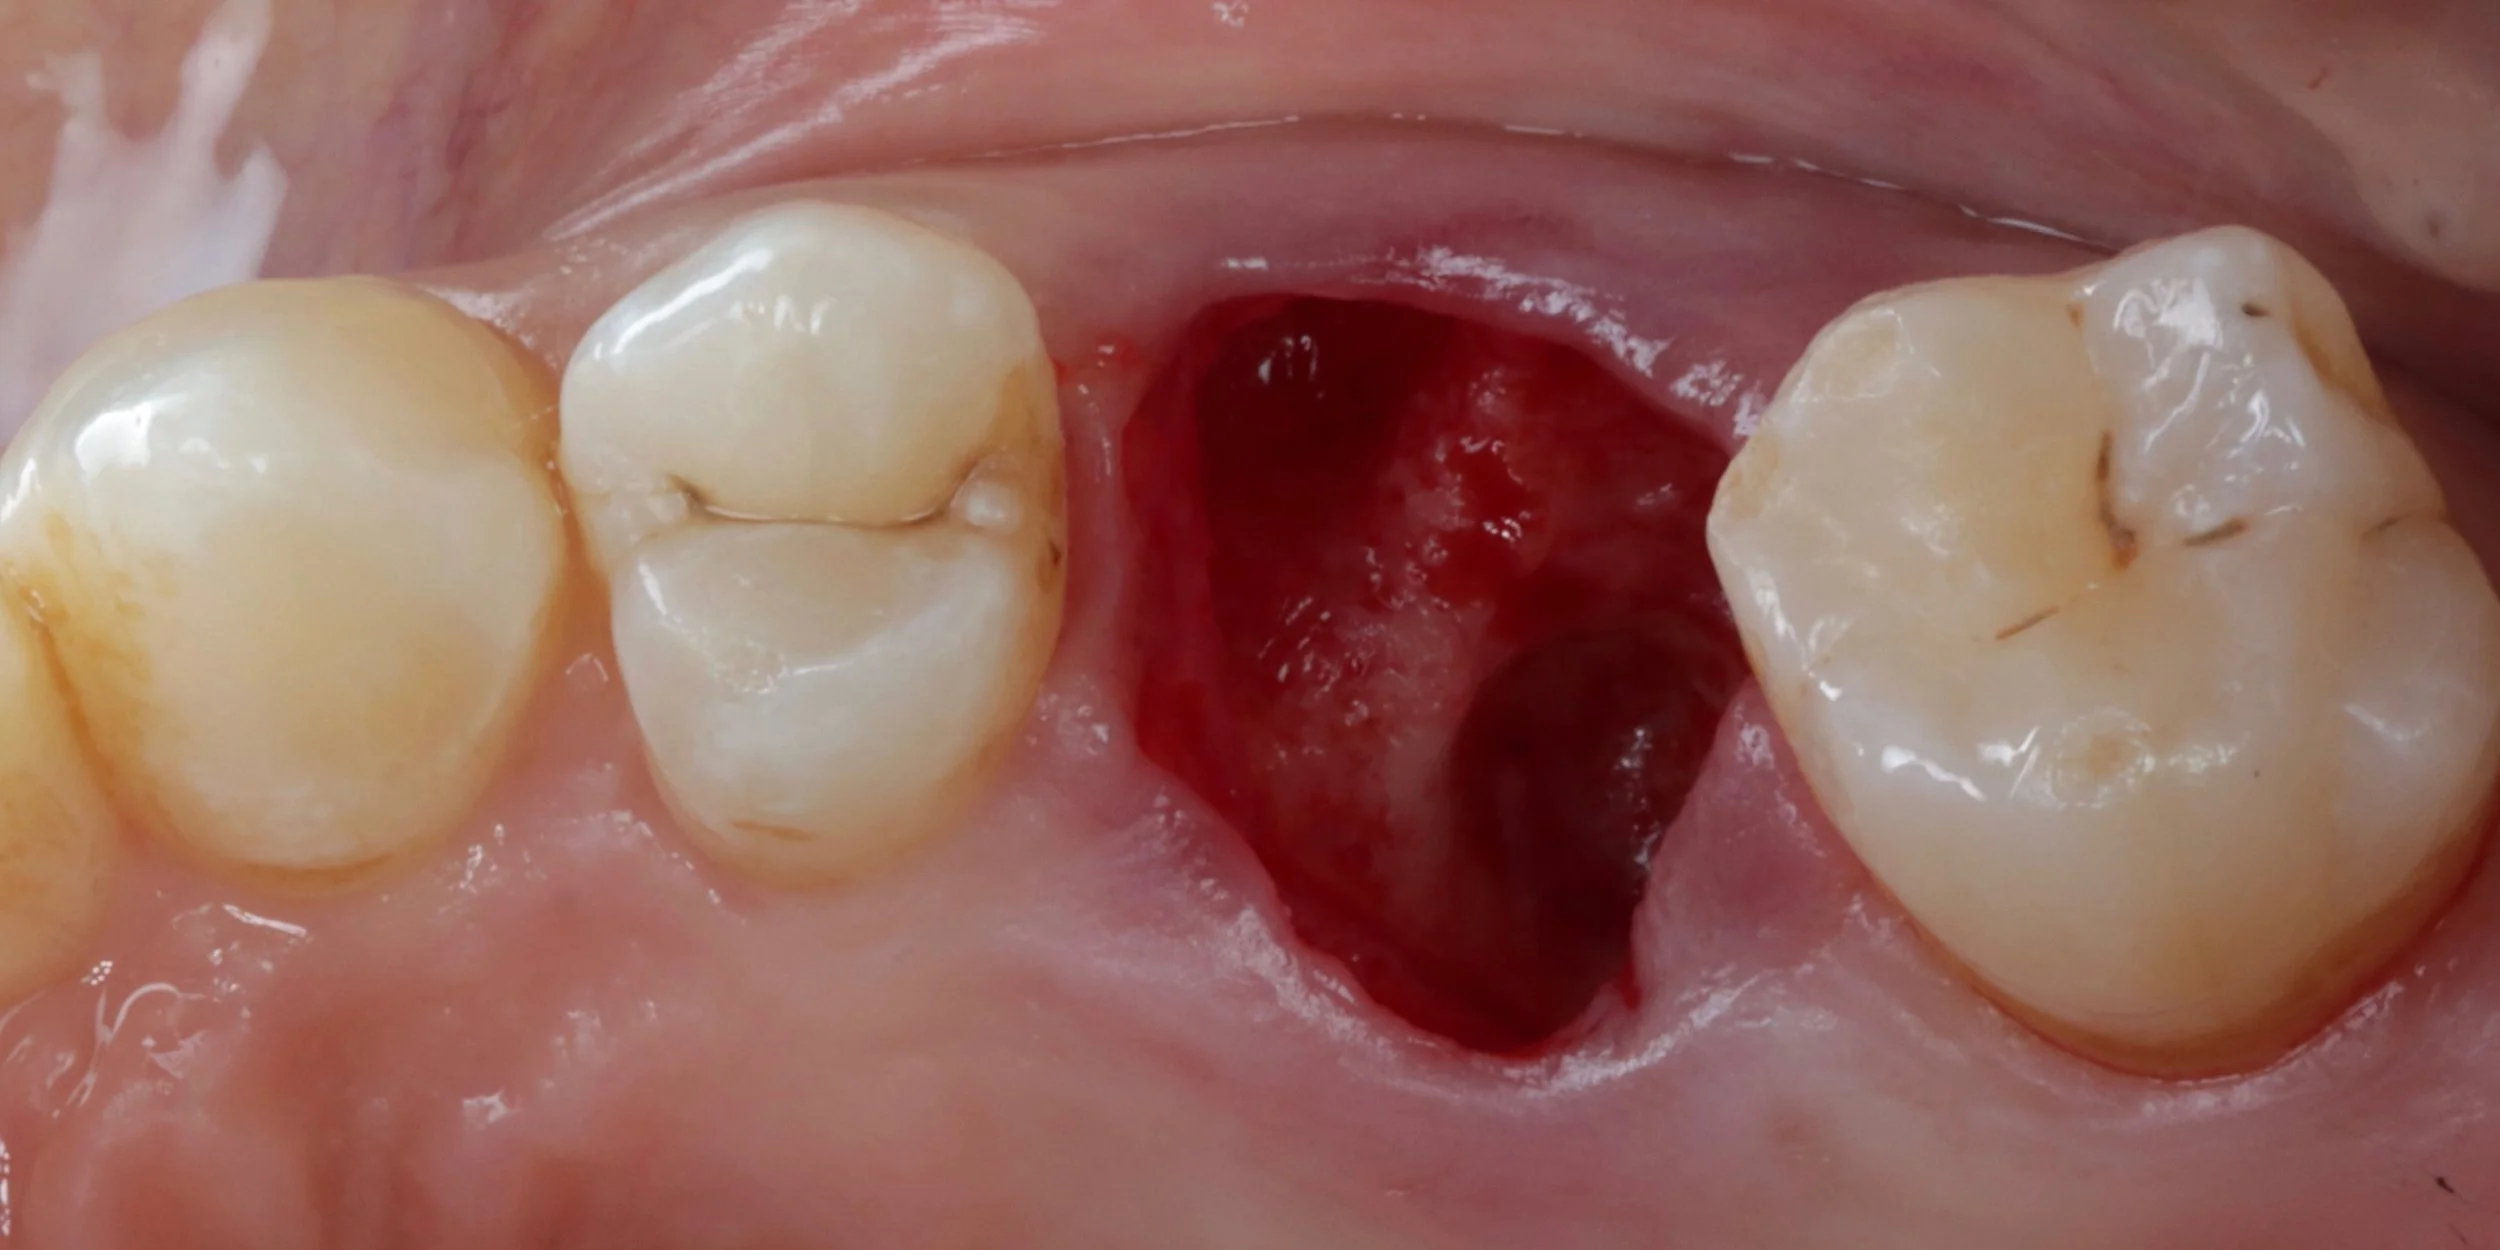

This under utilised yet highly valuable skill forms the foundations to help maintain gingival and alveolar architecture. From the general to the implant dentist, 15c will provide you with a predictable and simplified approach to ensure you can cultivate the ideal conditions for future implant or bridge placement for your patients. Learn surgical tips to improve your extraction and suturing techniques. Become confident in socket debridement and cleansing. Understand and see the different biomaterials available and the advantages and disadvantages of each. Practice how to use all of these skills to neatly and confidently perform socket preservation in practice.